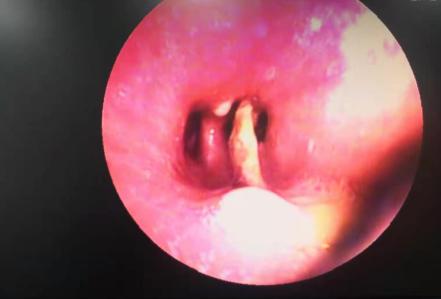

1月25日,科室主任、主任医师黄国民,副主任医师江焰平,护士长曹晖红,主管护师毛景丹等人密切协作,为鲍先生进行了手术,通过电子支气管镜准确找到了异物阻塞的位置,并成功取出了一根长约2cm的锯齿样鱼刺,与之前患者及家属回忆的情形相一致,终于确定了鲍先生长期咳嗽不愈的病因。1月27日,鲍先生的病情恢复良好并出院。